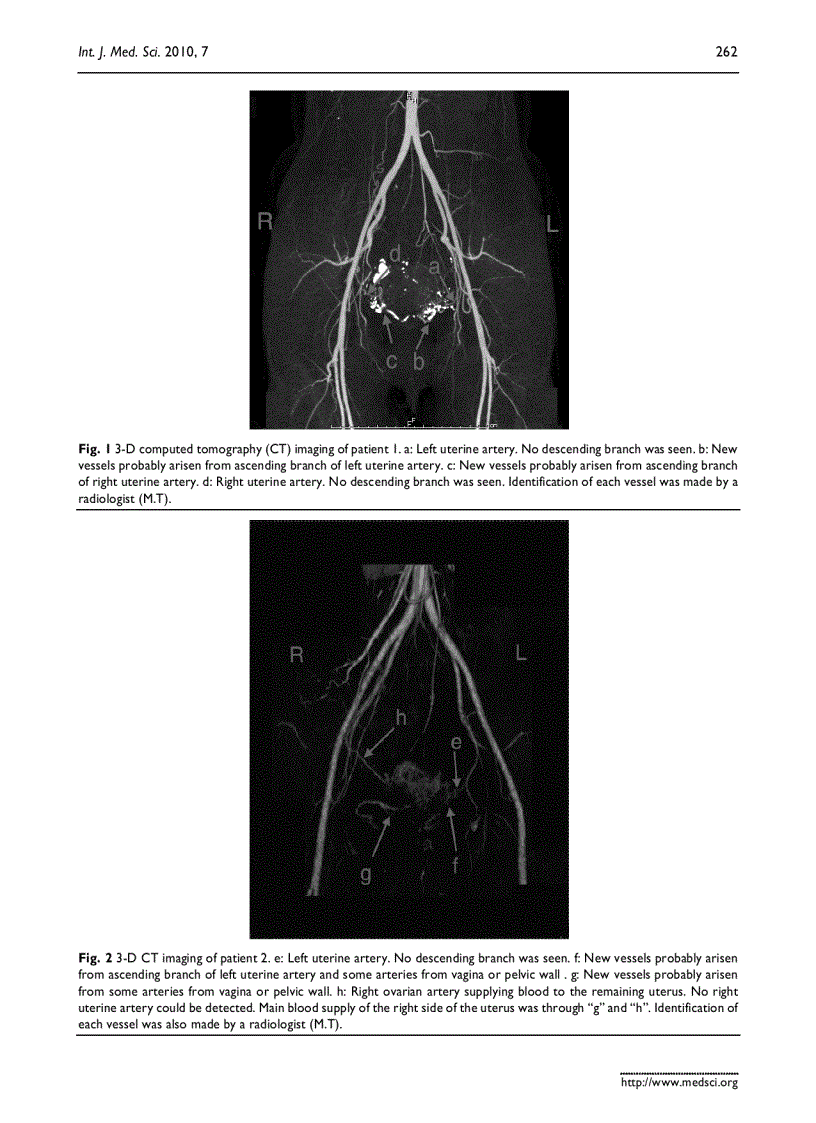

image for page Báo cáo y học Changes of uterine blood flow after vaginal radical trachelectomy VRT in patients with early stage uterine invasive cervical cancer